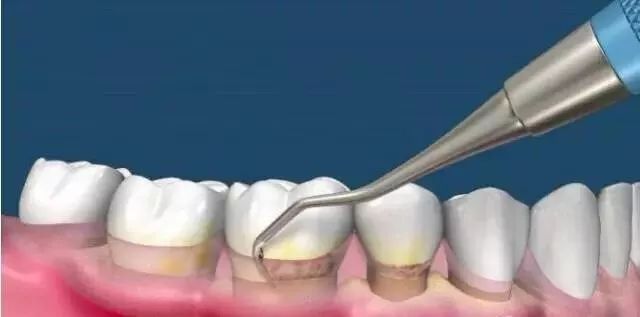

治疗牙周(非必需)

正畸前,医生需要确保你的牙周适合矫正,如果牙周不好勉强进行矫正的话可能会出现牙槽骨吸收等问题,所以牙周不好的童鞋需要在正畸前进行牙周治疗。同样的,有蛀牙什么的也需要先补好。